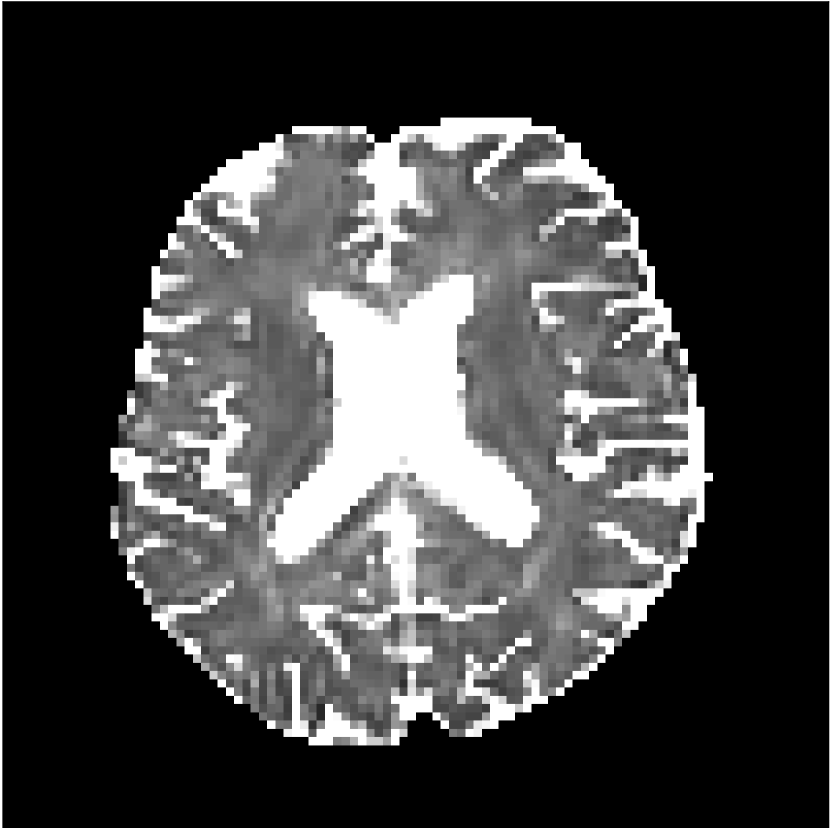

3.2 In Vivo Test Experiment Results

Figure 8 shows examples of non-diffusion-weighted images before and after processing. The raw images (Raw) served as the input for the magnitude deep learning (MCNN) and complex deep learning (CCNN) methods.

Raw

MCNN,

MCNN Resid.,

CCNN,

CCNN Resid.,

No PF

5/8 PF

Both methods remove artifacts, but the MCNN method allows residual rippling artifacts to pass through in the presence of partial Fourier. These rippling artifacts are not present in the CCNN method.